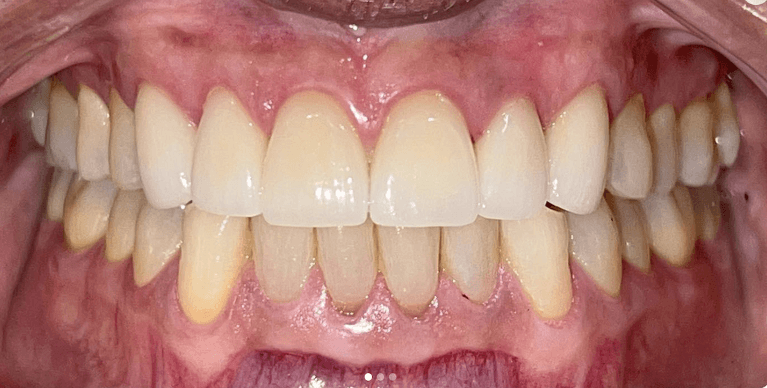

Upper & Lower, All on 4 fixed implant teeth with finals. Patient went home with temp fixed teeth the same day.